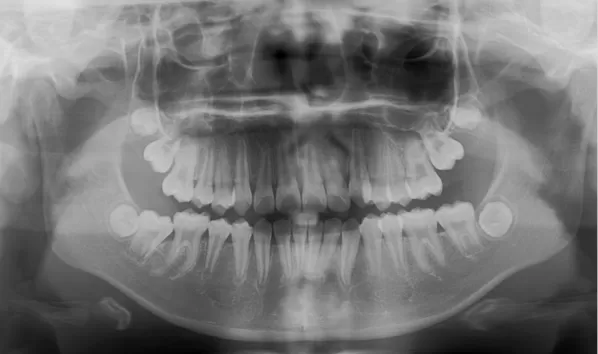

X-rays before treatment

[Panoramic Radiography/Lateral Cephalogram]